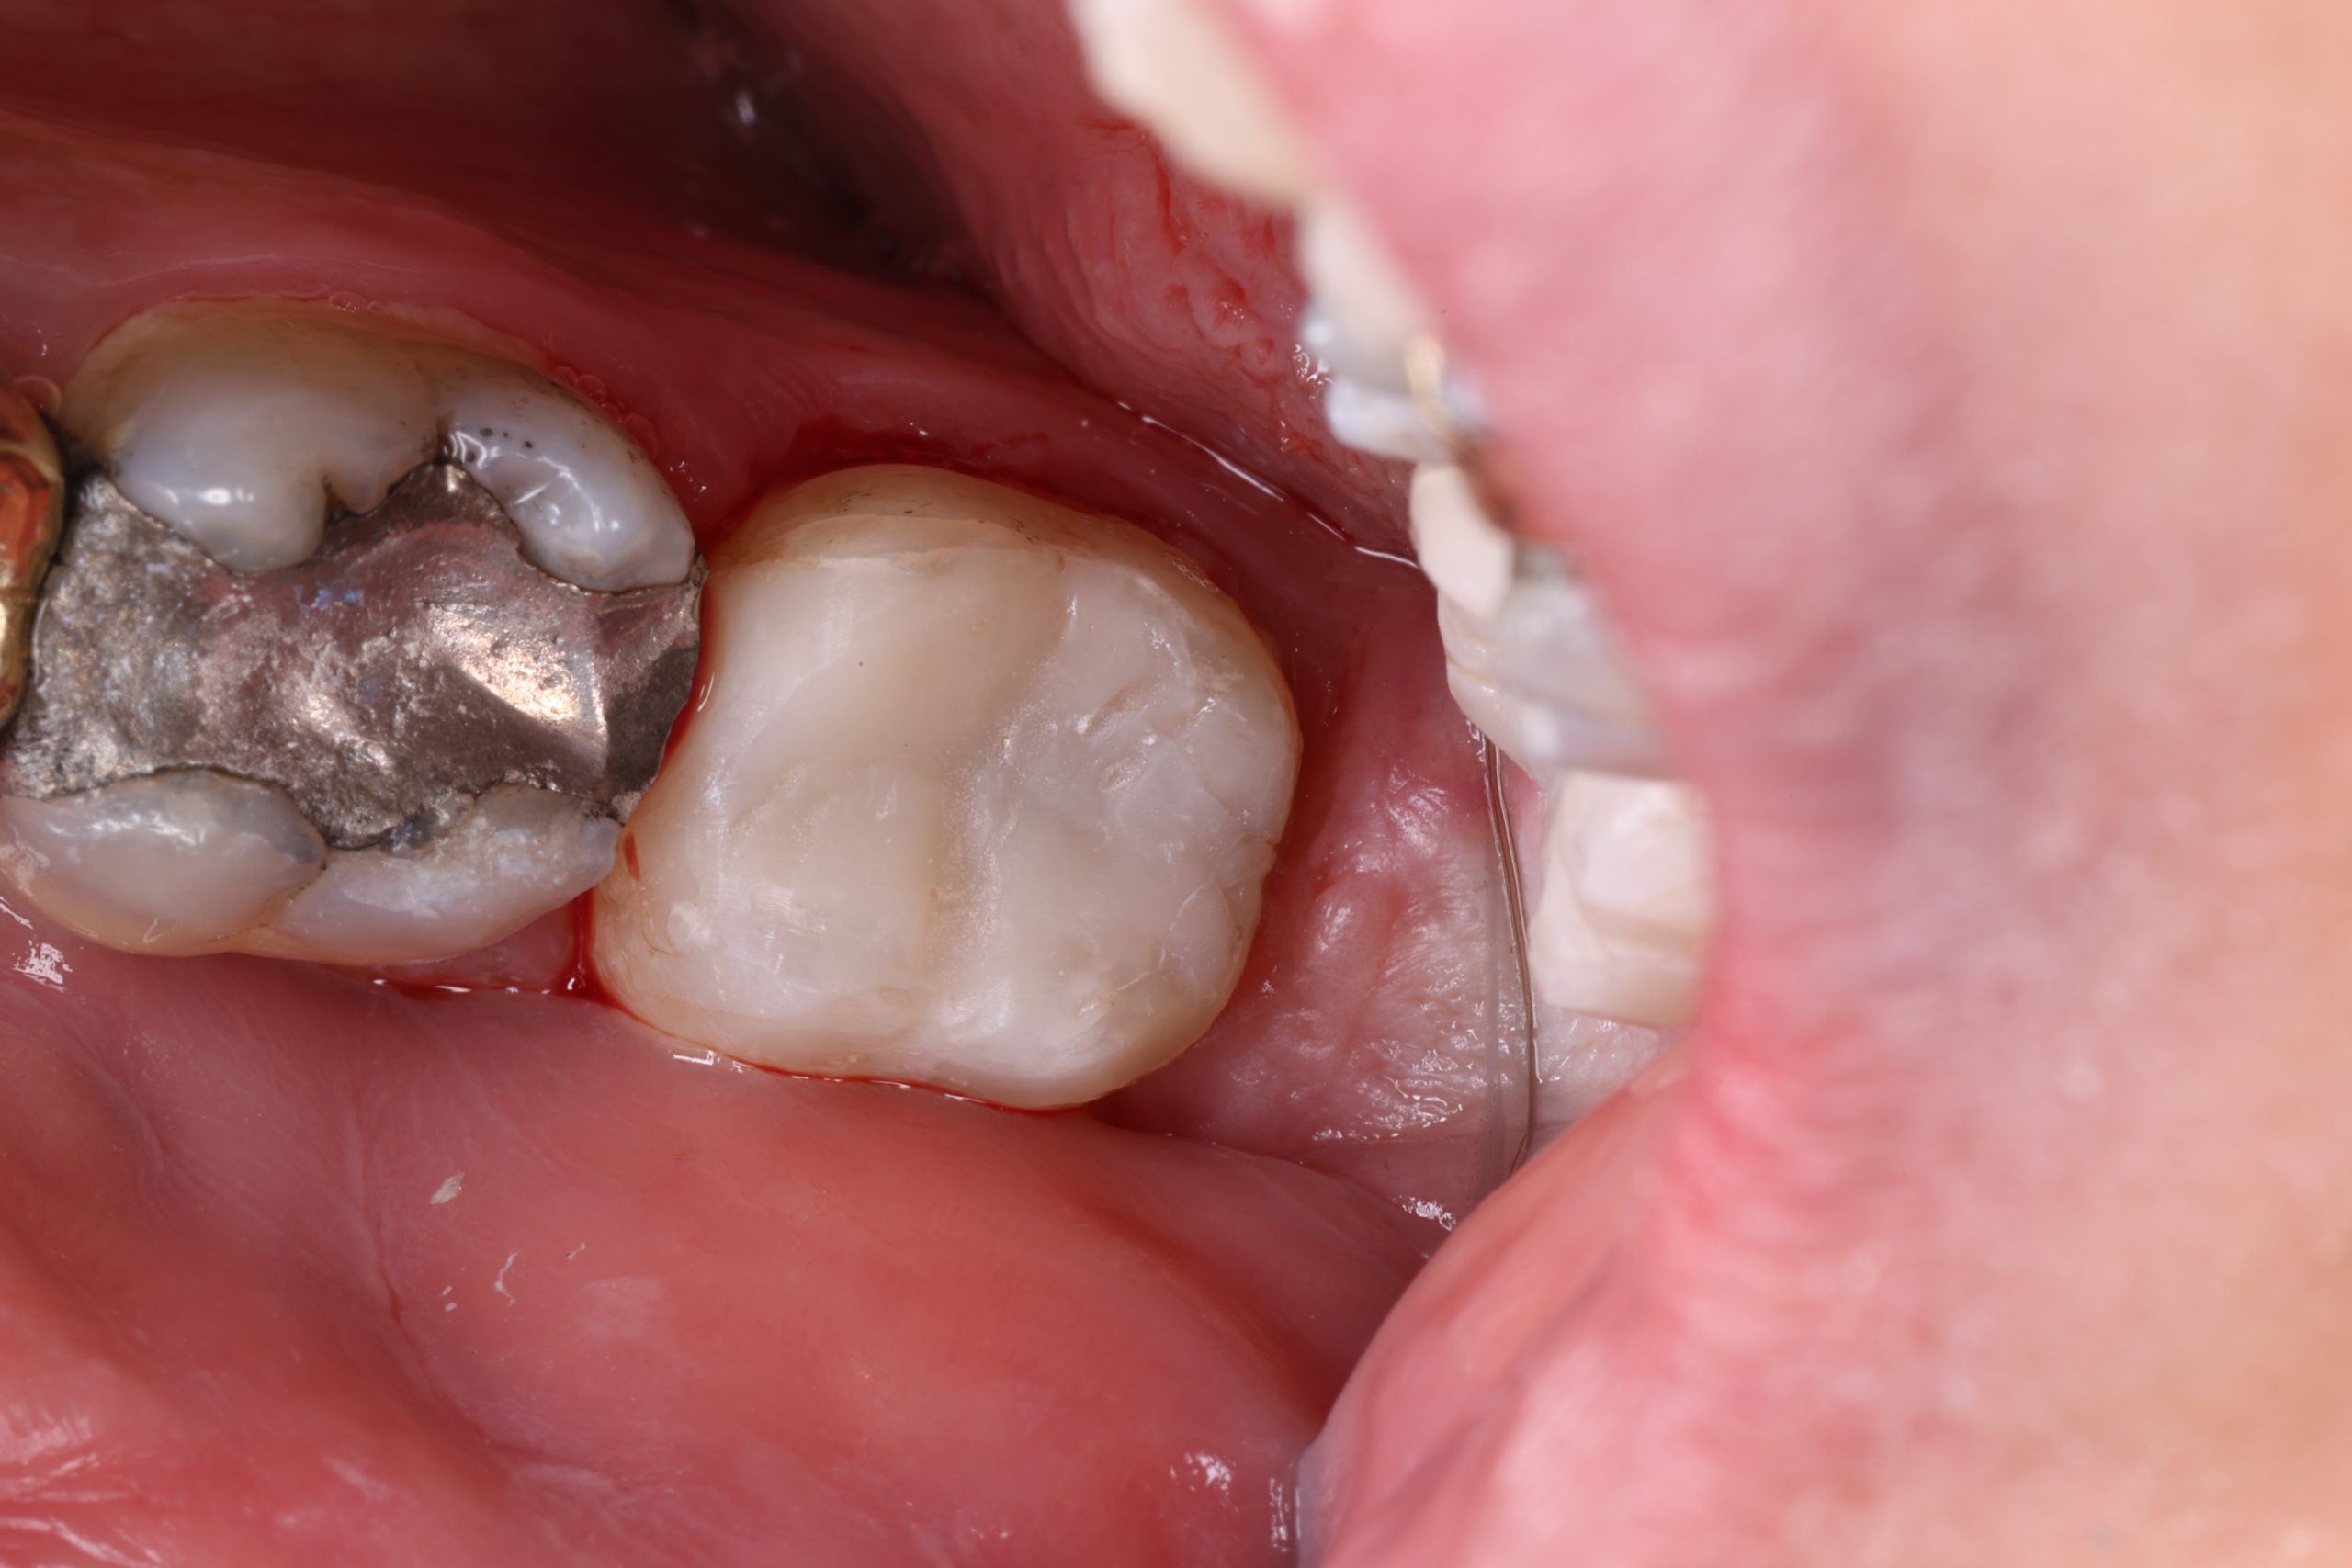

• replacing old metal fillings with a tooth-coloured option

For extensive damage or deeper cracks, we may discuss ceramic inlays, onlays, or crowns. Your dentist will recommend the most stable option based on diagnosis, not trends.